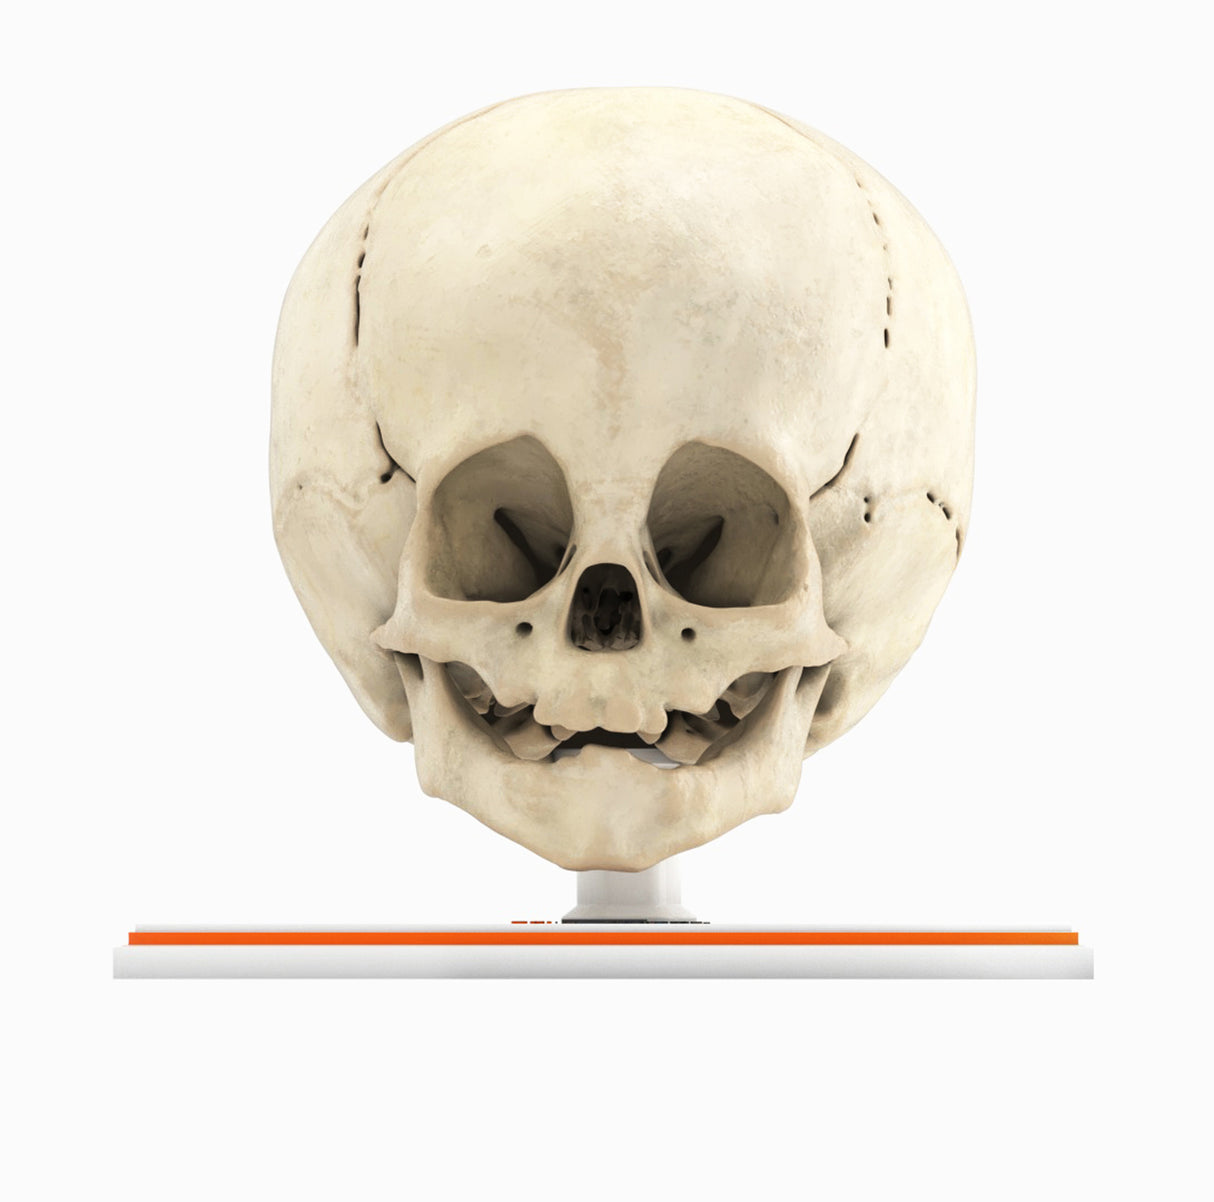

Infant Skull With Craniosynostosis of the Metopic Suture - Male, 8 Months

Infant Skull With Craniosynostosis of the Metopic Suture - Male, 8 Months

Craniosynostosis, a condition in which one or more cranial sutures in the infant skull prematurely mineralize and fuse before completion of brain development, with affected sutures:

Metopic synostosis (trigonocephaly) – The metopic suture separates two frontal bones in the cranial vault and runs from the nose to the sagittal suture at the top of the head. Premature fusion causes a triangular head shape, narrow in the front and broad in the back, with a metopic ridge at the midline of the forehead.

In most cases, the cause of craniosynostosis is unknown. Crouzon, Apert and Pfeiffer syndromes are the most common craniofacial syndromes, accounting for nearly two-thirds of syndromic cases. Most of these patients exhibit elevated intracranial pressure (ICP), hydrocephalus, optic atrophy, and respiratory, speech and hearing problems. Surgical management is common for primary craniosynostosis where there is restriction of brain growth and elevated ICP, typically within the first year of life.

Designed using MRI and CT imaging scans and the latest 3D printing technologies, in collaboration with Mayo Clinic.